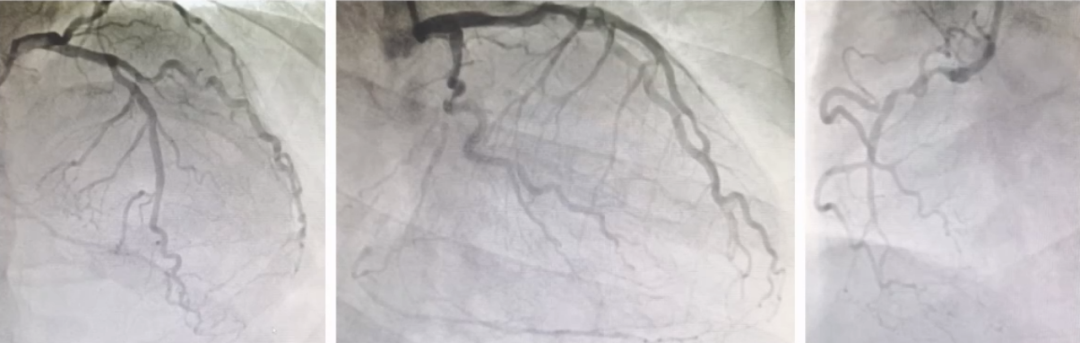

2022-10-26术前:患者右冠闭塞,回旋支狭窄。

2022-10-26术后冠脉造影如下所示:

由于考虑到FH,CX未进行支架植入,用药物球囊进行病变处理。